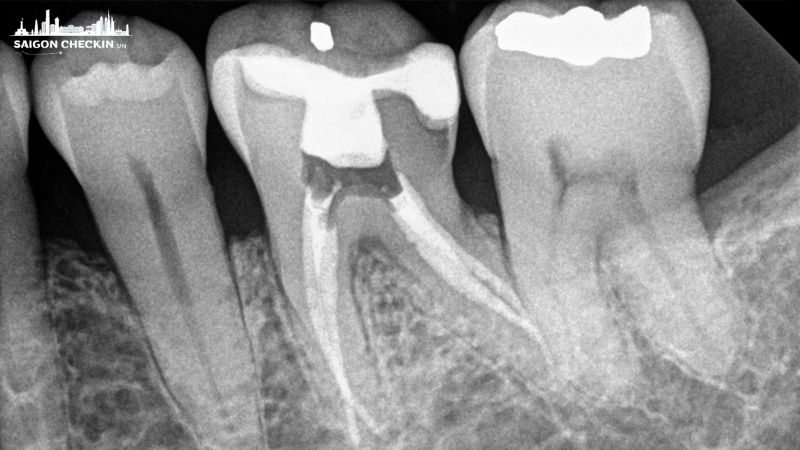

- Nha khoa Đông Nam: chuyên sâu về chữa tủy và phục hình răng, sử dụng hệ thống X-quang Conebeam 3D hiện đại, bảo hành dịch vụ rõ ràng.